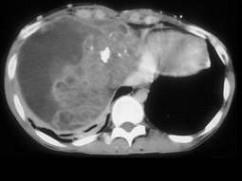

问题 男,37岁,咳嗽,咯血2月余,偶尔咳出钙化物,请结合影像学检查,选出最可能的诊断 ( )

选项 A、淋巴管瘤 B、淋巴瘤 C、肺癌 D、胸腺瘤 E、畸胎瘤

答案 E